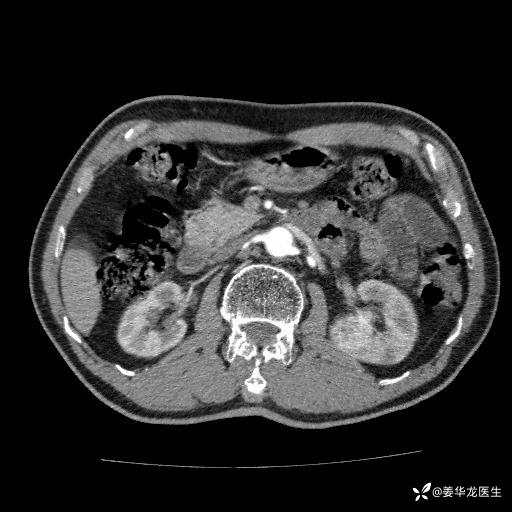

左肾中心型肾门部肿瘤39mm×34mm×36mm,右肾GFR25ml/min,部分切还是全切?

患者75岁老年男性,体重50kg,无高血压、肾病、糖尿病等基础病,检查发现左肾中心型肾门部肿瘤,右肾GFR只有25ml,无肉眼血尿,无镜下血尿。入院验血常规检查均正常,包括肾功能,肌酐102.7umol/L.

二、左肾肿瘤与左肾集合系、左肾动静脉关系密切,左肾部分切除术可行吗?成功率有多大?成功部分切后,肾功能还有多少?